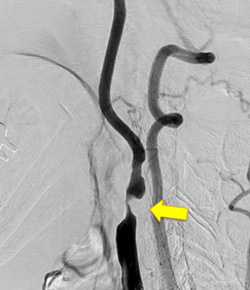

写真左:術前頚動脈狭窄所見

写真右:術後所見 外科手術によって頚動脈狭窄は改善している